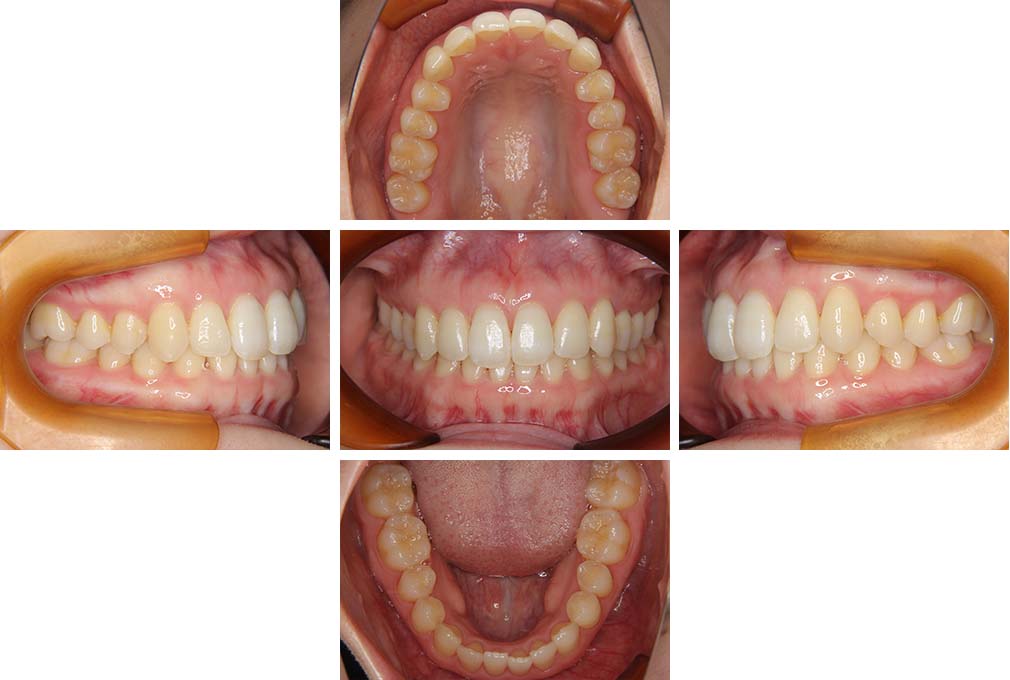

上下顎前突

初診時年齢 18歳4か月

性別 男性

治療費の目安 105万円程度(治療開始時)

歯列の乱れは著しくなく上顎右側側切歯が捻転し口蓋側へ転位していた。また、問診の中で患者さんから最も重視する治療結果として口元の突出の改善の申出があった。下顎が後退した上顎前突傾向ではあったが著しいものではなかった。上下顎前突と診断し上下顎小臼歯抜歯を行っていただき、上下顎舌側マルチブラケット装置を使用して、矯正用アンカースクリューを併用して動的治療を行った。上下顎前歯の後退を十分行い口元の突出感も改善した。治療後10年1か月の来院時には口元の突出感が再発することもなく、下顎前歯の少しの唇舌的なずれはあったが歯列は安定していた。動的治療期間2年2ヵ月間。

治療前

18歳4ヵ月

治療後

動的治療期間2年2カ月間

20歳10か月

10年経過

動的治療終了後10年1カ月

30歳11か月